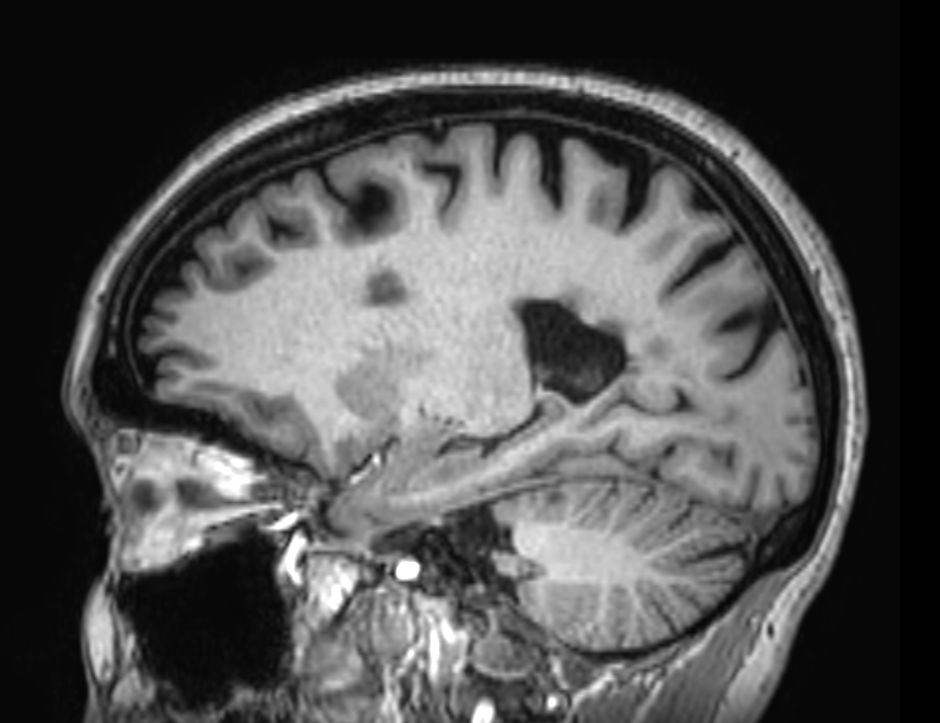

Multiple Sclerosis versus TIA

Standardized Multiple Slerosis MRI protocols typically require long scan times. Addition of Compressed SENSE enables faster exams, without compromise in image quality1. SWIp sequence has a high sensitivity to enhance contrast for deoxygenated (venous) blood or calcium deposits. This may help, when used in combination with other clinical information, in the diagnosis of various neurological pathologies. 3D (BrainVIEW) lets you acquire high resolution data in multiple directions in one scan. Isotropic voxel size enables reformats in any plane without loss of resolution.

3D T1w FFE (reformat) Compressed SENSE

-